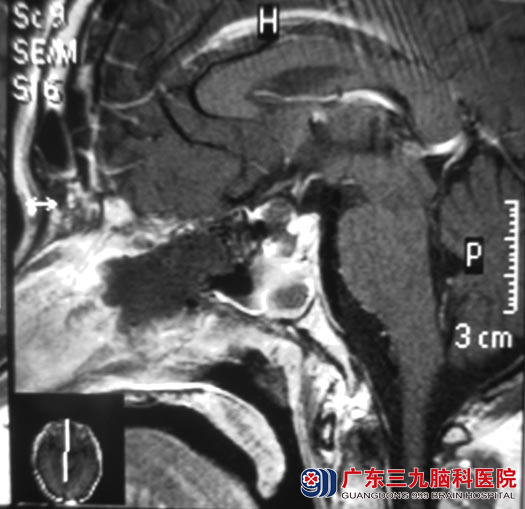

手术后